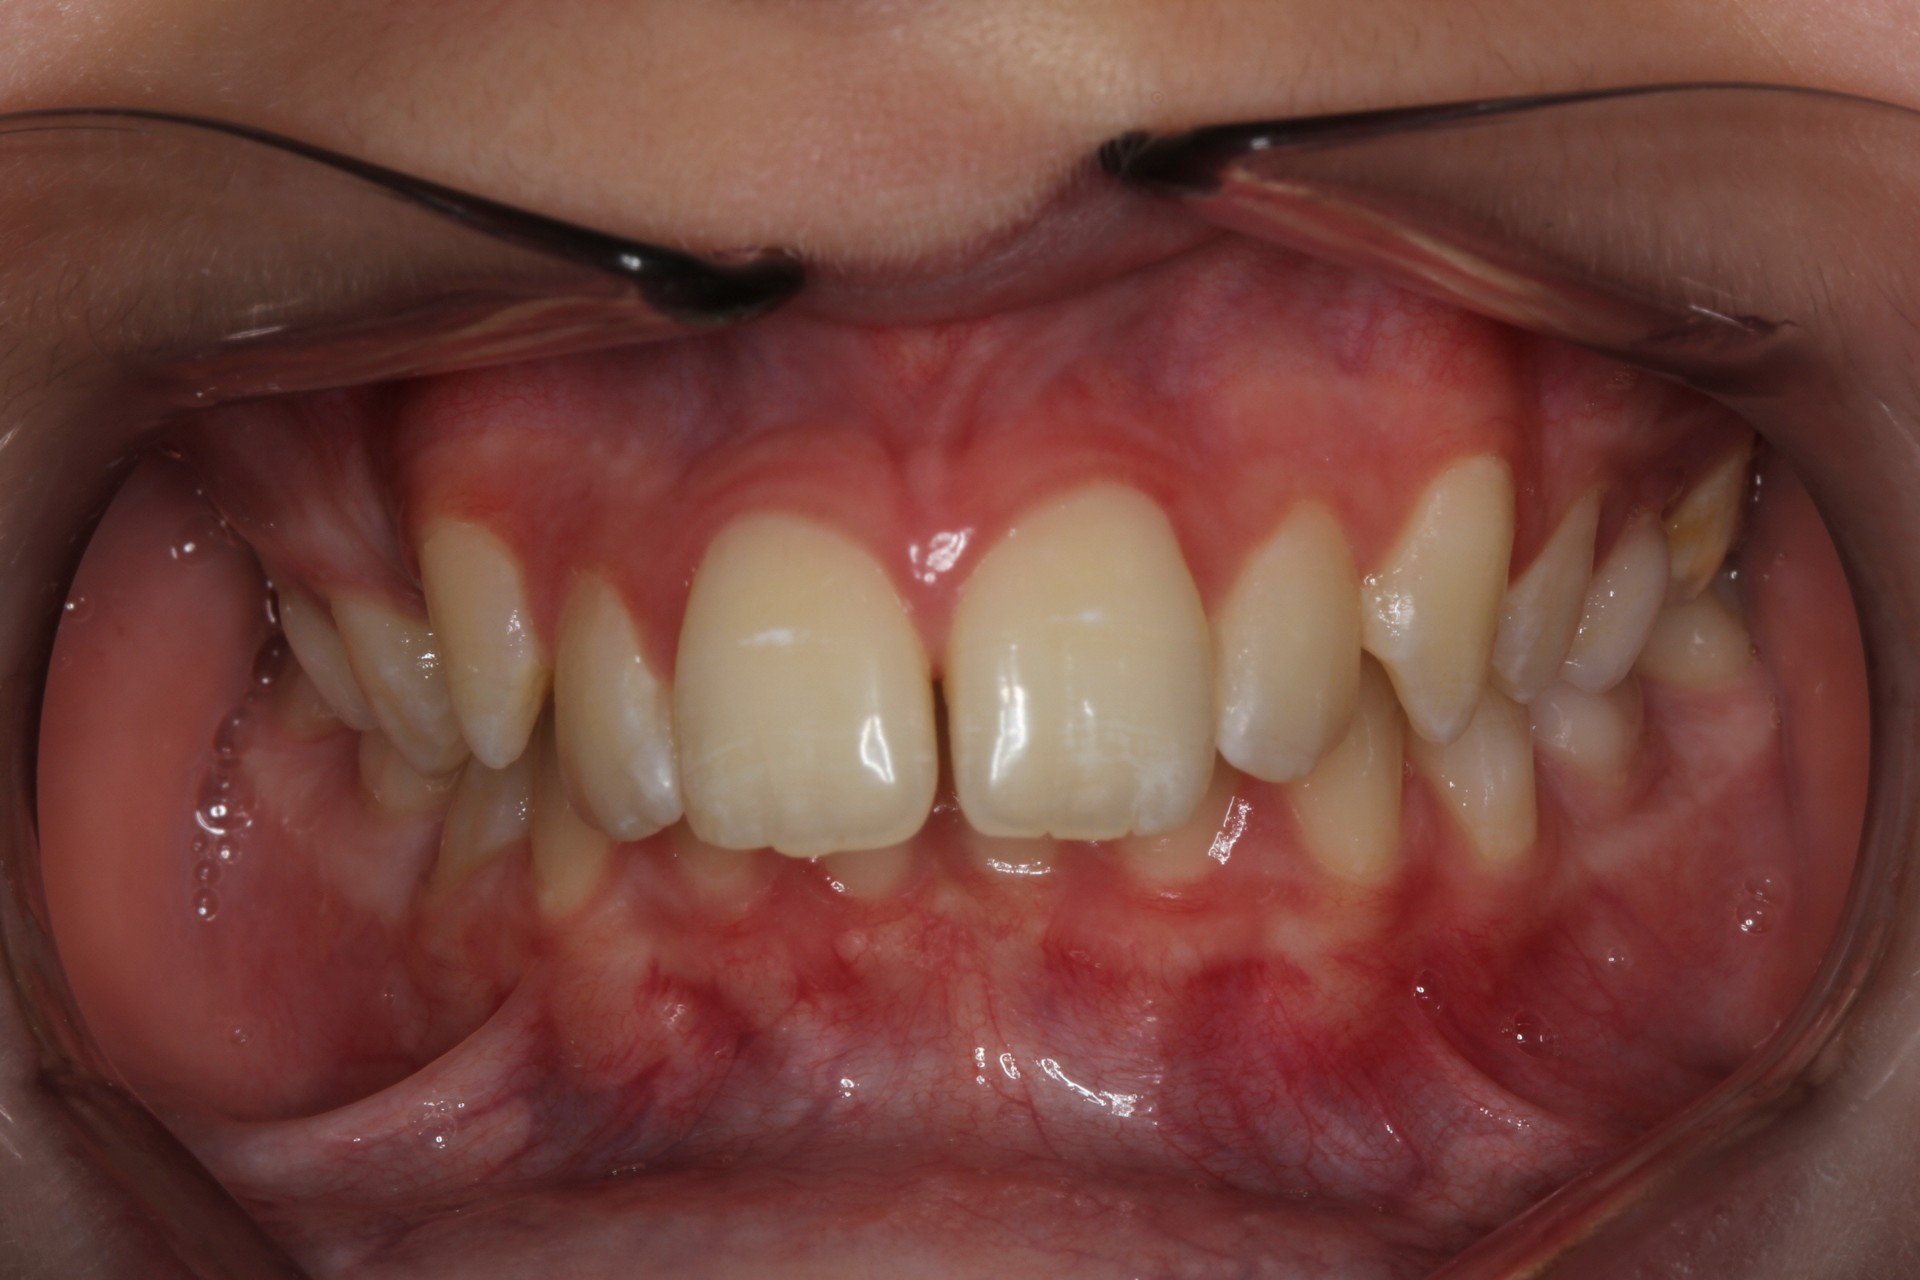

Protruding front teeth – Child case